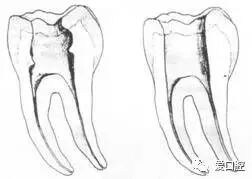

三、开髓孔

1. 正常开髓孔的位置和大小

左图为正常开髓孔的大小和位置。左边图为下颚,右边图为上颚。

2. 根管治疗中开髓孔的设计标准

根管治疗需去除髓腔内容物(去除髓室顶),建立所有根管的入路,允许冲洗液大量冲洗。开髓孔的设计标准以建立通路为目的,从而建立良好的视野和术野。

( 1 )直线通路:根管治疗时需要一个直线通路,直线通路能够达到根尖三分之一

牙胶尖什么颜色根管治疗的标准步骤以及治疗细节的把握_https://www.jmylbn.com_新闻资讯_第6张

测量标准:以允许根管器械直线并直接进入根尖 1/3 且不接触冠方各壁为标准。

( 2 )髓腔其他改变:如髓室顶、继发性牙本质、修复性或增龄性牙本质。见左图。

牙胶尖什么颜色根管治疗的标准步骤以及治疗细节的把握_https://www.jmylbn.com_新闻资讯_第7张

右图中有继发性牙本质,切削后获得直线通路